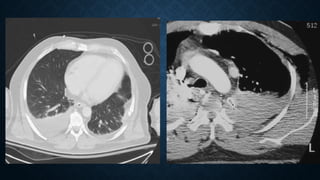

Pulmonary laceration in a 38-year-old man after a thoracic gunshot wound. (A) AP chest radiograph obtained at

presentation shows a hazy opacity in the left upper lobe, reflecting laceration obscured by pulmonary contusions. (B)

axial CT image obtained on the same day better shows the pulmonary laceration cavity filled with blood and air, with

surrounding contusion. (C) AP radiograph obtained 8 days later shows that the laceration is visible as a well-

circumscribed opacity, as the contusions have resolved. Note the persistent pneumothorax, possibly from a

bronchopleural fistula, a potential complication of large pulmonary lacerations.